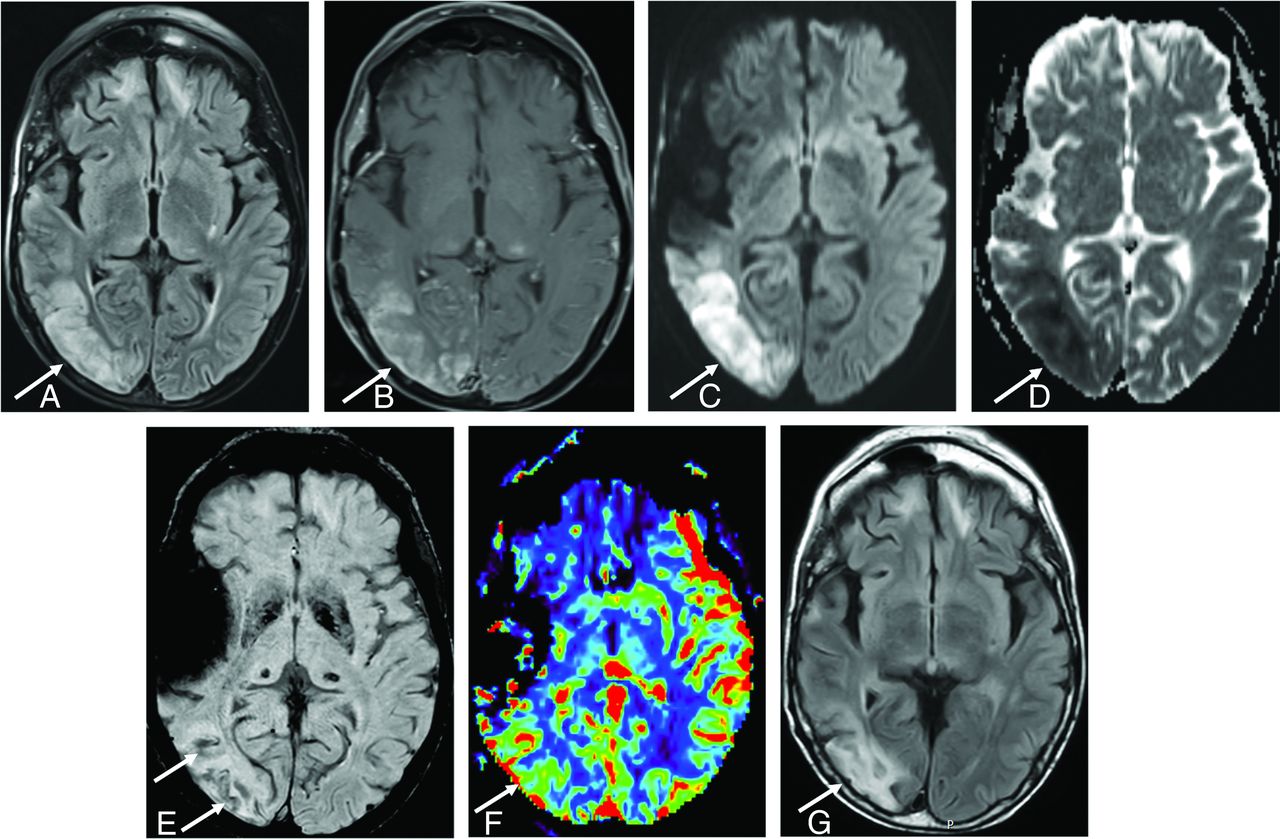

A 50-year-old man diagnosed with SMART syndrome. He had a history of pilocytic astrocytoma treated by resection and 60 Gy of radiation therapy 30 years ago and presented with left-sided hemiparesis, speech impairment, seizure, and migraine-like headache. He was diagnosed with SMART syndrome and treated by verapamil and aspirin, but residual symptoms (hemiparesis and speech impairment) remained. A, A FLAIR image shows cortical hyperintensity and involvement of subcortical white matter in the right temporo-occipital region (arrow). There is bifrontal subcortical white matter hyperintensity likely due to prior radiation injury. B, There is gyriform enhancement in the right temporo-occipital region (arrow) with restricted diffusion (C and D) (high signal on DWI and low signal on ADC) (arrow). E, SWI shows linear hypointensity along the subcortical white matter (arrow). F, Dynamic susceptibility contrast perfusion MR imaging shows an increase of CBV in the same area. G, After 3 months, FLAIR shows residual hyperintensity in the cortical and subcortical area (arrow).

In addition to classically described MR imaging features in the diagnostic criteria, white matter involvement adjacent to the gyriform enhancement and cortical swelling are observed in some cases, likely reflecting edema in severe SMART syndrome cases (Fig 3). The white matter involvement of SMART syndrome is suspected to portend worse recovery.5

SWI and T2*WI are sensitive to susceptibility effects of iron within hemosiderin29 and have been shown to identify microhemorrhage and radiation-induced intracranial cavernomas, which are commonly seen delayed complications of intracranial radiation therapy. SWI is more sensitive than T2*WI.30⇓-32 SWI and T2*WI show linear hypointensity in the subcortical white matter of the acute SMART attack region (Fig 3).5 There is no pathologic confirmation of this SWI white matter abnormality, but hemorrhagic transformation acutely affected by SMART syndrome is proposed.5 Also, patients with SMART syndrome with this SWI feature are suggested to experience incomplete recovery more frequently than patients without this SWI feature.5 Given that susceptibility imaging is consistently included in the routine brain protocol of many institutions, reporting of findings on SWI or T2*WI, even if negative, is important for radiologists and clinicians in terms of appropriate clinical management.

CT perfusion and DSC MR imaging findings have been reported in SMART syndrome. CT perfusion evaluates iodinated contrast passing from the intravascular to extravascular space of the ROI,33 and DSC MR imaging uses the first pass of a paramagnetic contrast agent through the ROI monitored by a dynamic series of T2- or T2*-weighted images.34 Both techniques allow assessment of local perfusion from first-pass contrast bolus analysis, including CBV and CBF. In the acute phase of a SMART syndrome attack, both CBV and CBF are increased (Fig 3), reflecting increased perfusion in the acute region,35⇓-37 while in the postictal phase, CBV and CBF are suggested to decrease or become normalized.35,38 This perfusion pattern can help distinguish SMART syndrome from other etiologies such as local recurrence or carcinomatosis, which typically manifest as persistent elevated perfusion in the absence of targeted treatments, warranting sequential perfusion imaging.